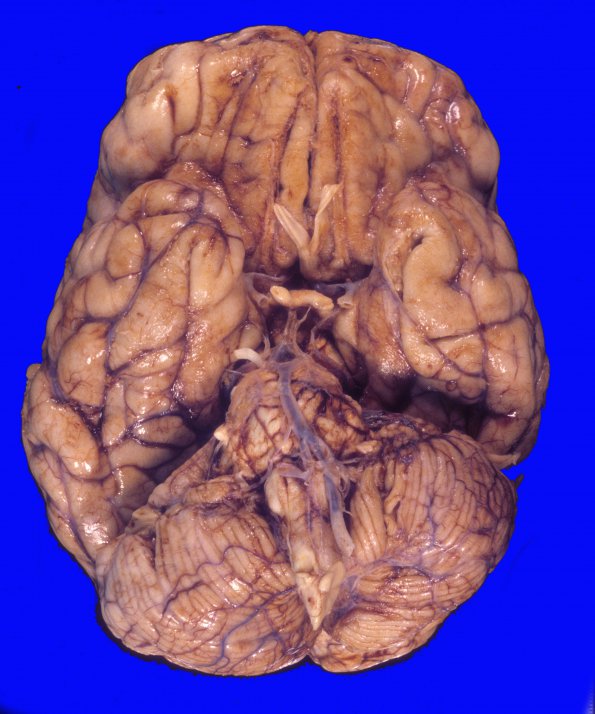

The ventral exterior surface of the brain fails to show substantial pathology.